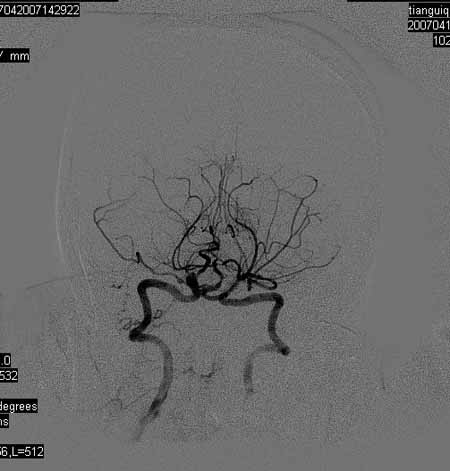

标题: DSA0093:脑血管造影

女,63岁,左侧额、枕叶脑梗塞。

右肾动脉及左颈内动脉起始部狭窄(考虑动脉硬化引起的),大脑中动脉分支减少.